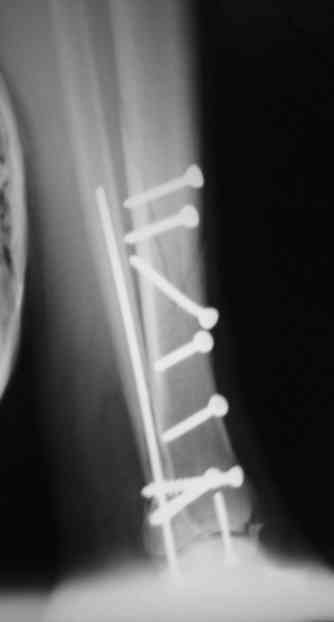

Сегодня прооперировали. Длительность 4-50. Начали как и говорил сверху вниз линейным разрезом - фиксация задне-латерального отломка к проксимальному 2мя винтами, затем "прилепили" к ним передне-медиальный (пришлось повозиться - была интерпозиция и довольно "сложный" винт) - к проксимальному 1 винтом и к задне-латеральному 1 винтом.Кстати на фото видно - у передне-медиального отломка еще осколок в области сустава, несколько смят. Далее началось веселье - второй доступ - задне-наружный к латеральной лодыжке и заднему краю, но оказалось, что задний край больше задне-медиальный (по снимкам было непонятно). Плюс к этому репозиция его мягко говоря сложновата (больной на спине, стол низкий и не поднимается). В общем выставили, фискировали 2мя винтами, на ЭОПе вроде стал, только верх отошел. Латеральную лодыжку заведующий решил интрамедуллярно (не хотел еще винты толкать), сначала 3мм спицей - нестабильно, затем 4мм стержень (не помню по автору) - ОК (кстати в месте перелома мелкая крошка - дефект до 5х7 мм по кортикалу). Ну медиальная лодыжка стандартно - третий разрез - винт 3,5 мм. Визуально все стабильно. На Р-контроле - видна небольшая ступенька заднего края по одному из контуров.

Рентгенограммы

На фото простой суставной, метафиз. оскольчатый с переходом на диафиз перелом, пластина MIPO.